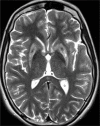

Figures